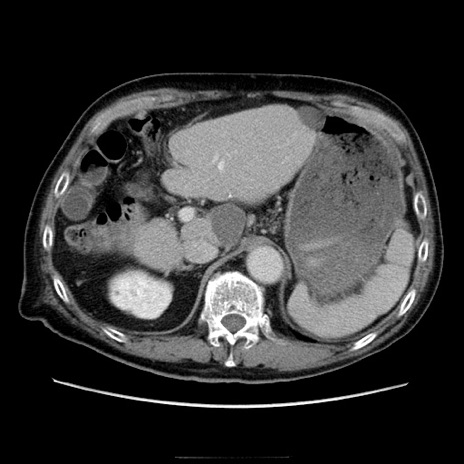

症例21(横断像)

【症例】70歳代男性

【主訴】腹痛

【現病歴】肝硬変・肝細胞癌にてかかりつけの方。約9時間前に食後より腹痛出現。症状が徐々に増悪し、嘔吐出現したため来院。

【既往歴】肝硬変、肝細胞癌(RFA、TACE後)

【身体所見】意識清明、表情苦悶様、BT 36℃、BP 129/78mmHg、P 88bpm、SpO2 97%(RA)、右上腹部から心窩部にかけて圧痛あり、反跳痛なし、筋性防御あり。

【データ】WBC 5800、CRP 0.16